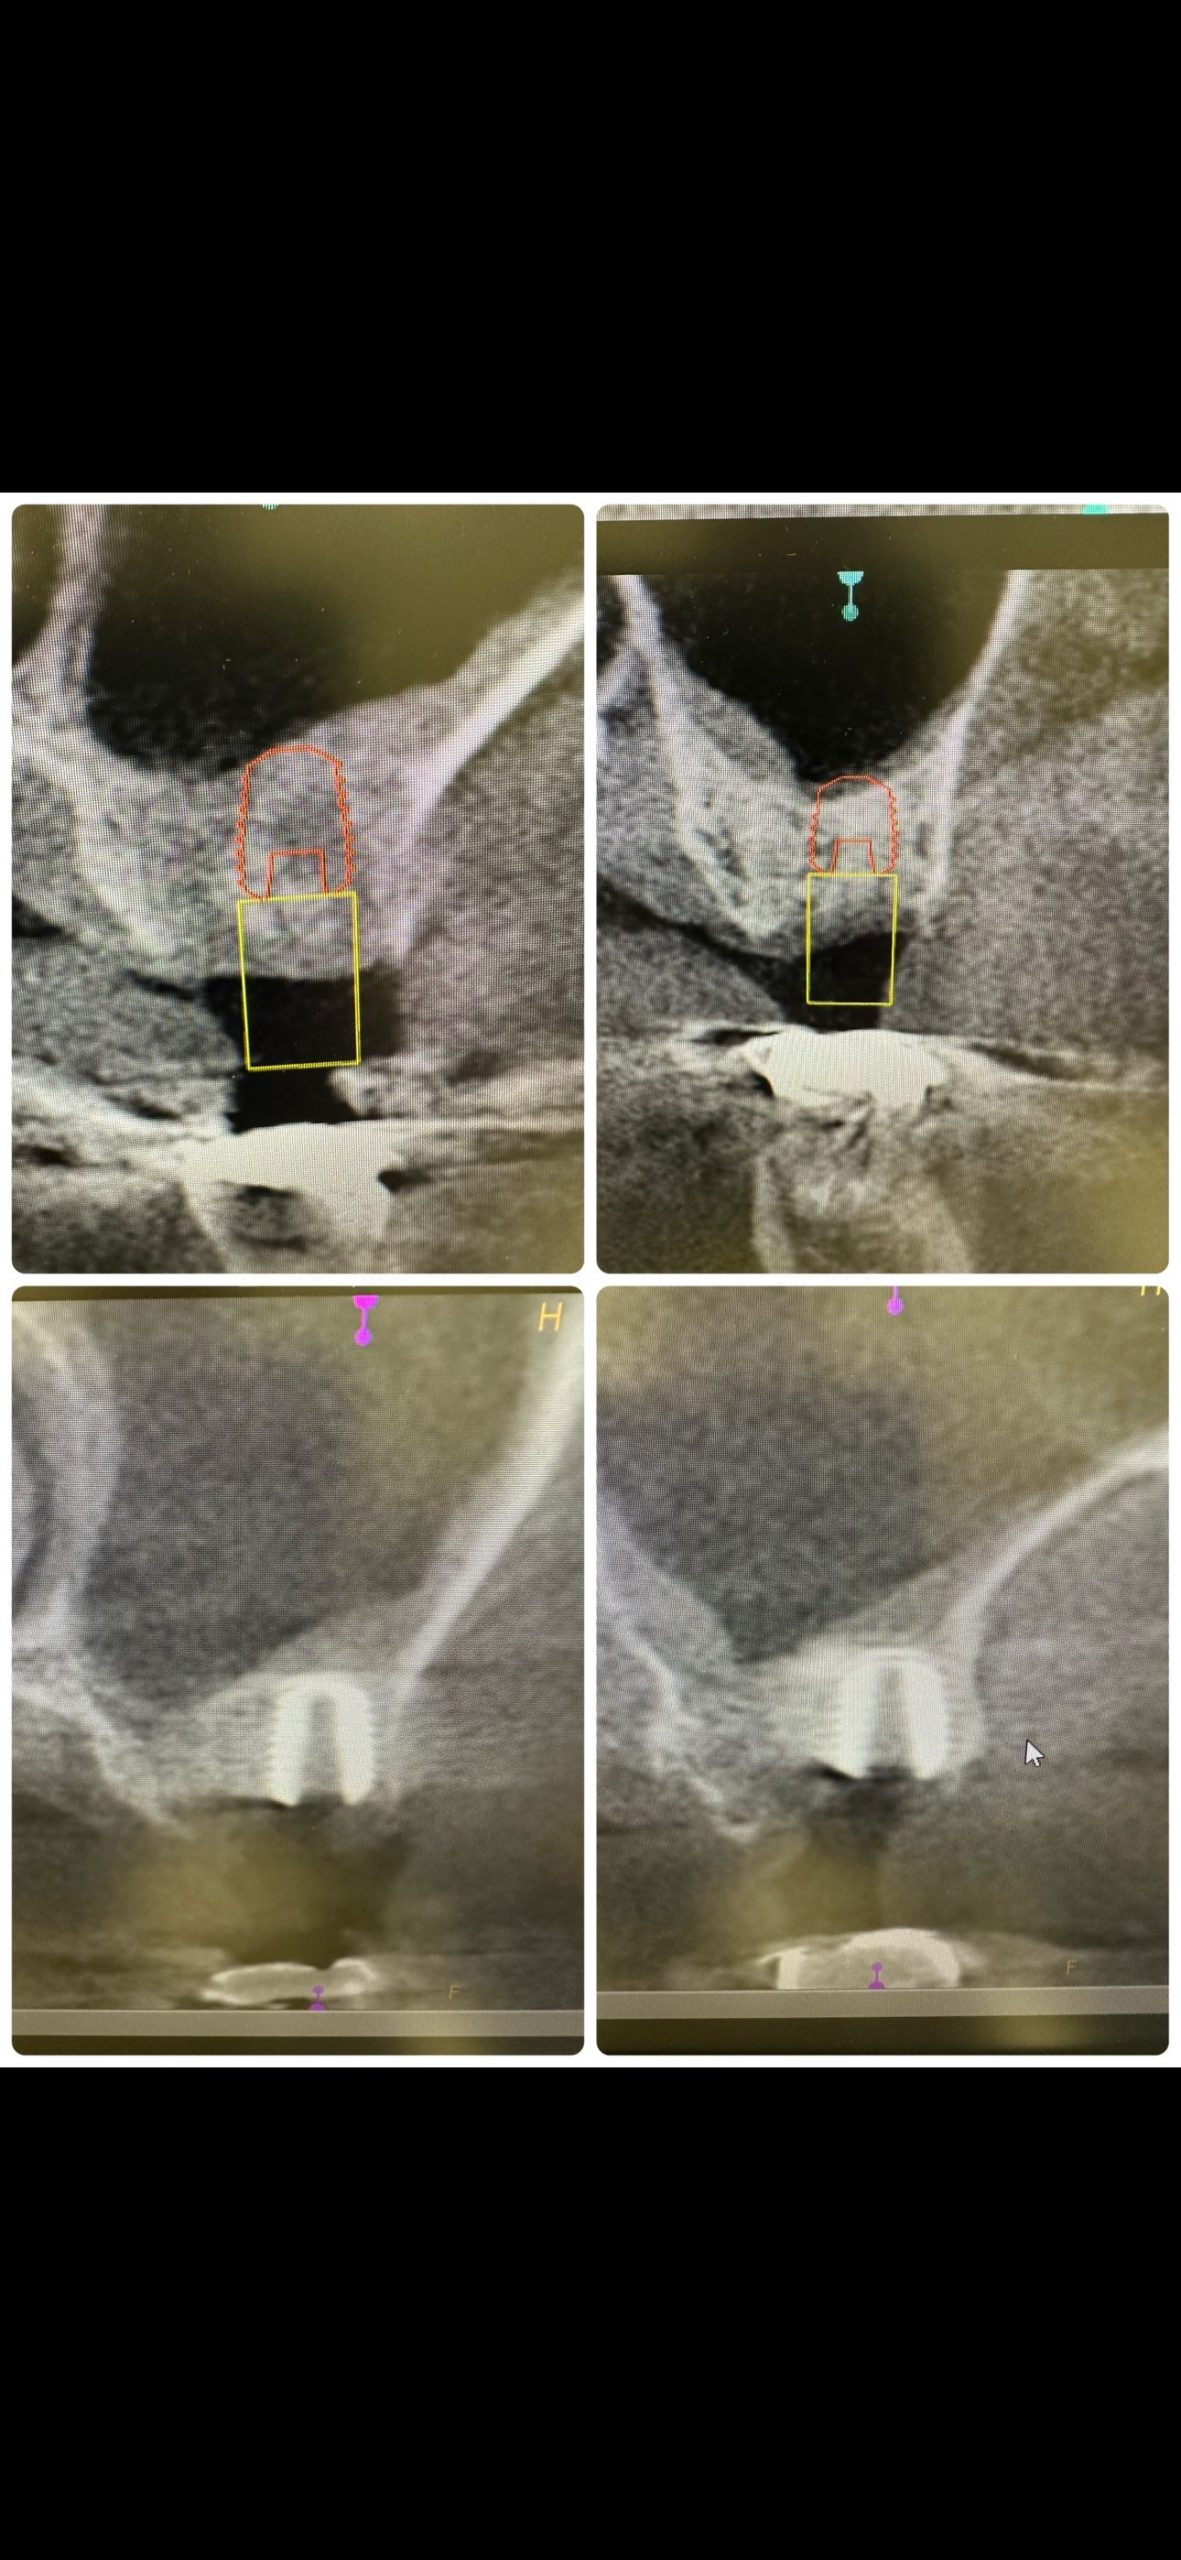

次は昼休み利用し、大変お世話になった方の息子チャン

56歳

デンサーリフト、難なく30分で終わり💪

ISQ.I TV共にクリアー、6w後には仮歯

年内には噛めるようになる💪